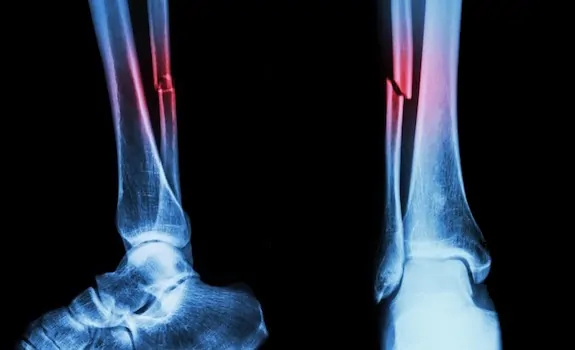

Es la ruptura total o parcial de un hueso por diversas causas; lo más común es que se deba a un accidente, una caída fuerte o una lesión deportiva. La fractura provoca un dolor intenso y dependiendo de la gravedad puede necesitar cirugía para recomponer el hueso.

Fracturas por estrés

Son las que se dan al ejercer presión de forma repetitiva en los huesos. Se pueden distinguir dos tipos:

●  Fracturas por debilidad: por haber algún tipo de deficiencia ósea que debilite los huesos, como la osteoporosis.

●  Fracturas por fatiga: a causa de una actividad exagerada y repetitiva. Es frecuente en los deportistas o en aquellas personas que realizan actividades físicas de manera frecuente.